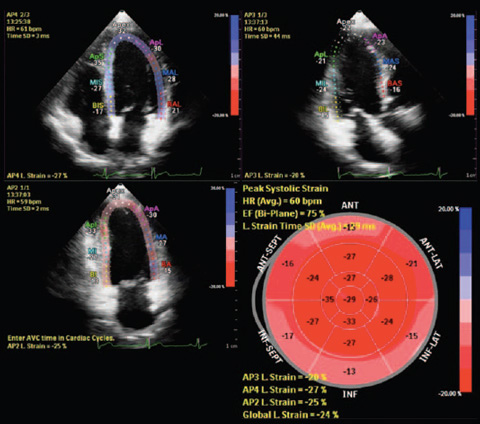

HeartModelᴬ⋅ᴵ⋅— это новое приложение для УЗИ с технологией интеллектуального анализа анатомии (AIUS), предлагающее передовые средства количественной оценки трехмерных данных в реальном времени, автоматизированное создание двумерных проекций и уверенное получение воспроизводимых результатов в эхокардиографии. Приложение HeartModelᴬ⋅ᴵ⋅ автоматически определяет, сегментирует и количественно оценивает левое предсердие (ЛП) и левый желудочек (ЛЖ) в трехмерных объемных данных.

Согласно результатам сравнительного исследования двумерного количественного анализа и анализа в режиме Live 3D HeartModelᴬ⋅ᴵ⋅ приложение HeartModelᴬ⋅ᴵ⋅ позволило сэкономить 82% времени при работе в полностью автоматическом режиме и 71% времени при минимальном ручном редактировании.

Благодаря повышенной воспроизводимости и выполнению меньшего количества этапов за меньший промежуток времени, чем требуется для традиционных методов, больше пользователей смогут увереннее проводить диагностику.